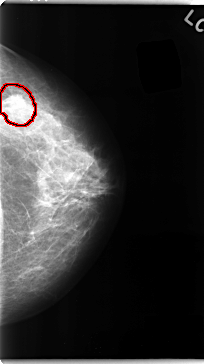

C_0097_1.LEFT_CC

LEFT_CC LINES 4728 PIXELS_PER_LINE 2640 BITS_PER_PIXEL 12 RESOLUTION 50 OVERLAY

FILE: C_0097_1.LEFT_CC.OVERLAY

TOTAL_ABNORMALITIES 1

ABNORMALITY 1

LESION_TYPE MASS SHAPE IRREGULAR MARGINS SPICULATED

ASSESSMENT 5

SUBTLETY 5

PATHOLOGY MALIGNANT

TOTAL_OUTLINES 1

BOUNDARY